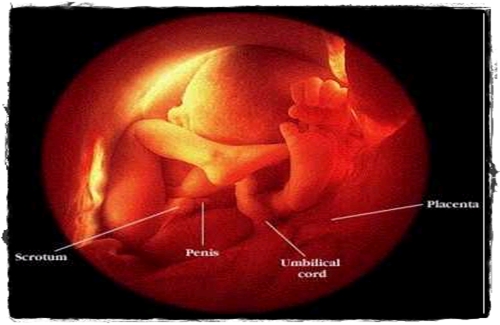

ภาพครรภ์อายุ 8 เดือน อวัยวะสมบูรณ์เกือบ 100% แล้ว

การตั้งครรภ์เดือนที่ 8 ในขณะที่ลูกกำลังสนุกกับการเคลื่อนไหว แต่คุณแม่ของเรานี่สิเริ่มทรมานกับการเคลื่อนไหว เพราะท้องขนาดใหญ่ยังทำให้คุณแม่เดินอุ้ยอ้าย หรือแม้แต่จะลุก นั่ง นอนก็แสนจะลำบาก หายใจก็ไม่ค่อยสะดวก มดลูกขยายทำให้ยอดของมดลูกอยู่สูงถึงซี่โครงชิ้นล่างสุดและดันกระบังลมของแม่ขึ้นไป ทำให้อึดอัดหรือรู้สึกว่าหายใจไม่พอ นอกจากนี้แม่จะเริ่มอ้วนขึ้น แต่อ้วนอันนี้ไม่ได้มาจากท้อง ที่ใหญ่ขึ้นนะ แต่อ้วนเพราะเกิดจากการบวมของอวัยวะต่างๆ ที่มีของเหลวมาสะสมอยู่ เช่น ใบหน้า มือ ขา ริมฝีปาก เป็นต้น (จะคลอดเราออกมาแล้ว แม่ก็ยังไม่ได้สวยอีก!!) ตอนนี้ทั้งสมองและร่างกายของลูกเรียกได้ว่าพัฒนาจนสมบูรณ์ ทั้งภายใน เช่น ปอด หรือ อวัยวะภายนอก เช่น แขนขา นิ้วมือที่มีเล็บขึ้นเต็มพอดี อวัยวะเพศก็มีครบสมบูรณ์ ตอนนี้ลูกๆ อย่างเราก็เหมือนรู้งาน จะหมุนตัวกลับเอาหัวลงไปที่เชิงกรานของแม่ เพื่อเตรียมสำหรับคลอดในเดือนหน้า แต่บางคนก็ดื้อนะไม่ยอมกลับหัวมา ก็เดือดร้อนแม่ของเราต้องผ่าตัดอีก ><!!